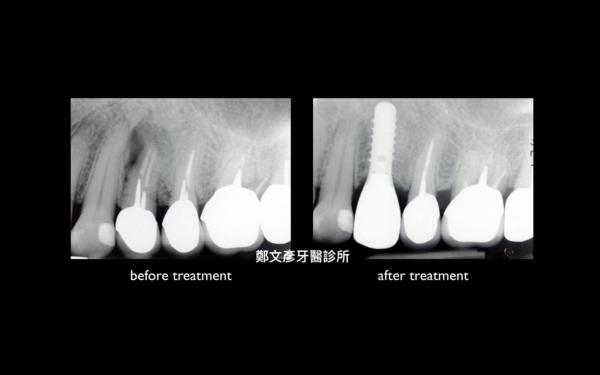

Role of granulation tissue in socket preservation

3. Role of granulation tissue in socket preservation